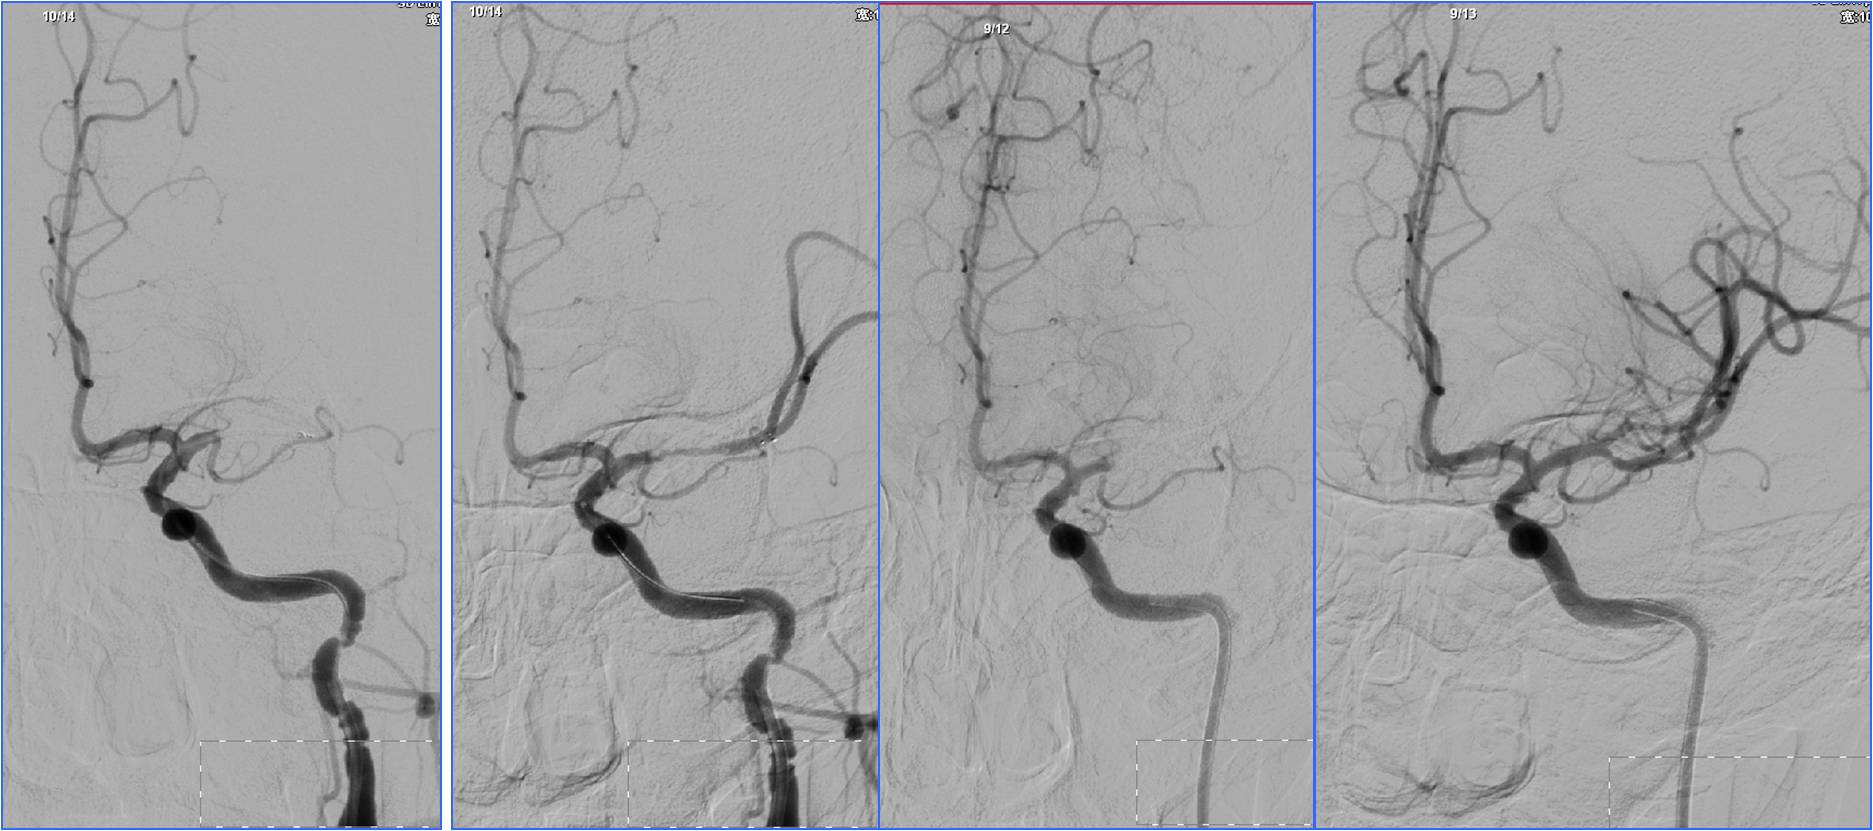

Case3 椎动脉开口支架置入

》男,68岁,有长期吸烟史。

》6:30突发晕厥1次伴头晕,7:00到急诊。7:30突然发作肢体抽搐伴意识不清。于8:10收入神经内科ICU。

》查体:血压140/60mmHg。中度昏迷,双侧瞳孔散大,光反应消失。四肢肌张力增高,去脑强直状态。双侧巴氏征阳性。NIHSS评分35分。

》昏迷前头CT检查(7:22)未见明显异常。

》昏迷后行头MRA检查。

▼7:22头CT

▼8:36头MRA

》急查血常规、凝血四项、肝肾电糖。

》签署静脉溶栓+动脉溶栓治疗知情同意书。

》8:54给予阿替普酶静脉溶栓,5mg静推,余45mg持续泵入。

》10:00股动脉穿刺。行气管插管全身麻醉。

▼于基底动脉远端及双侧大脑后动脉,分次给予阿替普酶共计5mg。

》12:10结束手术,带气管插管返回神经内科ICU。给予乌拉地尔持续泵入控制血压在110/70mmHg左右。

》第二天6:00出现中枢性高热,体温40℃。3天后转入普通病房。

》20天后出院,NIHSS评分5分。

▼溶栓后MRI